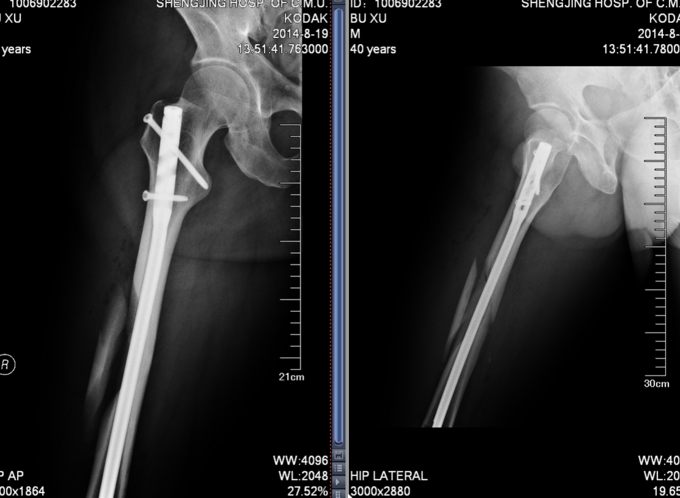

患者于2014-8-14 13:30左右,工作时不慎被重物砸伤,当时无法站立,自觉头晕,意识清楚,自觉大腿部疼痛,无法活动,被急送往我院急诊,经检查诊断为“右股骨干骨折”,给予对症处置,并请我科会诊,现患者为进一步诊治,转入我科病房,我科以“右股骨干骨折”为诊断收入院,患者伤后无昏迷,无恶心呕吐,无呼吸困难,至今未排便排气

右大腿肿胀,活动受限,压痛(+),骨擦音(+),骨擦感(+),可见异常活动,患肢皮肤感觉较健侧未见明显异常;足趾活动灵活,肌力正常,末梢循环可,足背动脉可触及。

诊断:右股骨干骨折 患者入院后急诊行右胫骨结节骨骼牵引术,术后维持患者长度,减轻患者疼痛,完善相关检查后,行右股骨干骨折闭合复位髓内针内固定术。